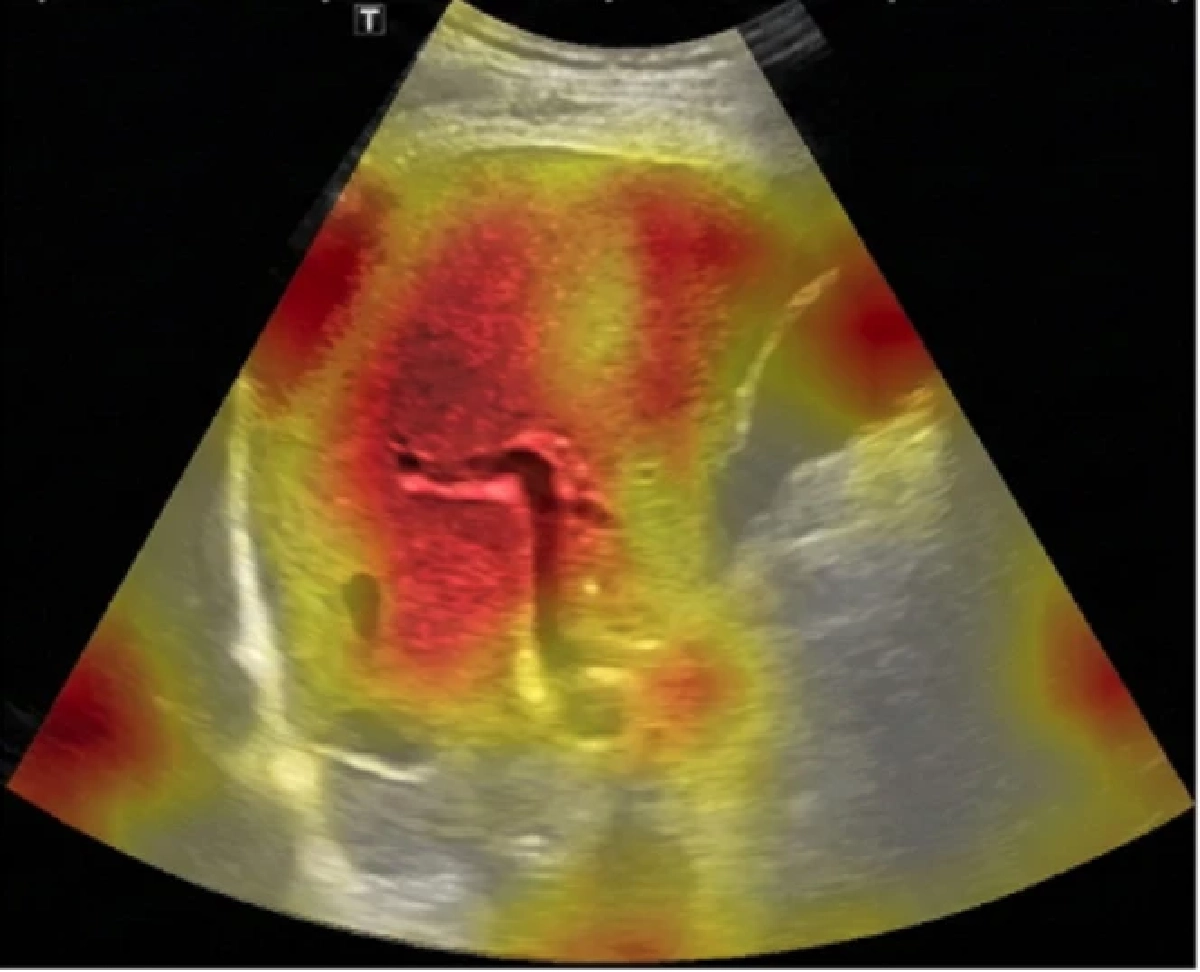

พวกเขาสร้าง SmartLiva ระบบ ‘AI อัจฉริยะ’ ทำงานเหมือนอัปเกรด ที่เปลี่ยนเครื่องอัลตราซาวด์ขาวดำธรรมดาๆ ที่มีอยู่แทบทุกโรงพยาบาล ให้กลายเป็นเครื่องมือวินิจฉัยประสิทธิภาพสูงเทียบเท่าเครื่องราคาล้านบาท สามารถอ่านภาพอัลตราซาวด์ได้แม่นยำและรวดเร็ว โดยแพทย์อัปโหลดภาพผ่านเว็บได้ทั้งบนคอมพิวเตอร์หรือแท็บเล็ต จากนั้นระบบจะช่วยปรับภาพให้ชัดขึ้น คัดเฉพาะบริเวณเนื้อตับที่ต้องวิเคราะห์

SmartLiva อัลตราซาวด์เสร็จใน 7 วินาที ด้วยความแม่นยำในการตรวจระยะตับแข็งสูงถึง 92% ตรวจเนื้อเยื่อผิดปกติได้แม่นยำ 87% และตรวจพยาธิใบไม้ตับได้แม่นยำถึง 84%